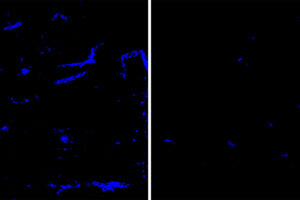

The burden of Alzheimer’s disease doesn’t fall on all communities equally. Black Americans face about double the risk of developing the devastating neurodegenerative disease than non-Hispanic white Americans do.

Racial equity in Alzheimer’s research focus of $7 million in grants (Links to an external site)